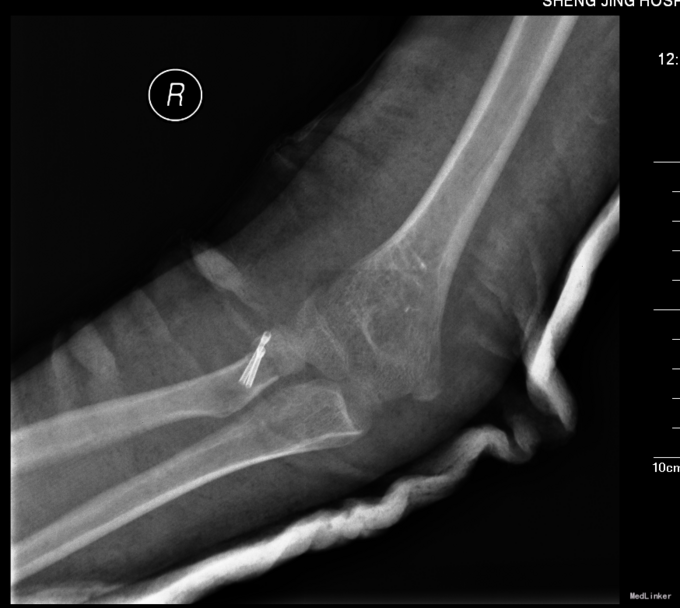

患者入院后肘关节肿胀明显,消肿约1周后,查无明显手术禁忌症后,全麻下行左桡骨小头骨折空心钉内固定术。术后给予患者石膏固定,定期换药,14天后拆线出院,建议石膏固定4周。